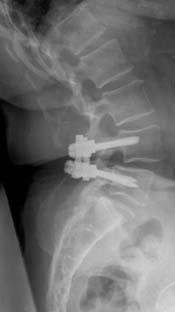

X-ray of spinal fusion

In spinal fusion, screws and rods are often used to help stabilize the spine.